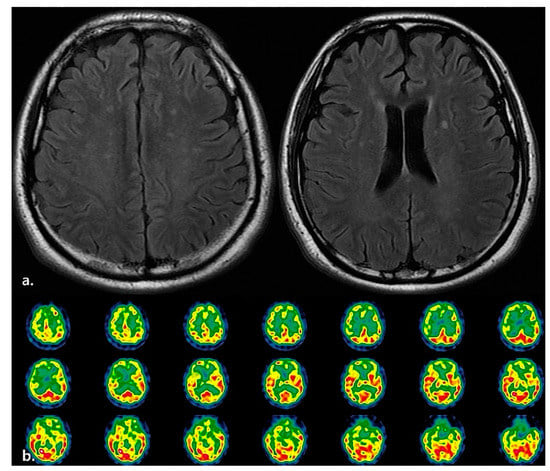

| 2 | 32 | F | Autoimmune encephalitis | Admission (29 January 2021) | 0 | 0 | 0 | 5 | L-tube |

| RM transfer (13 May 2021) | 0 | 0 | 0 | 5 | L-tube | ||||

| AC diagnosis (15 May 2021) | 0 | 0 | 0 | 5 | L-tube |